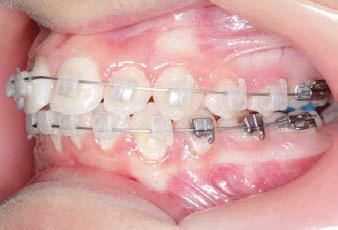

CLASS II DIV.1 - Marra

INITIAL - 4/4/18

PROGRESS 1 - 26/9/18 - Class I platform accomplished in 5.75 months with Motion 3D COLOR Appliance

PROGRESS 2 - 26/9/18 - Placement of the SLX 3D Clear Brackets

with M-ONE .015 Cu Nitanium 27°

PROGRESS 3 - 30/10/18 - With M-TWO .020 x .020 Cu Nitanium 35° archwire

PROGRESS 4 - 27/11/18 - 3 links power chain: 5, 4, bypass 3 to crimp hooks